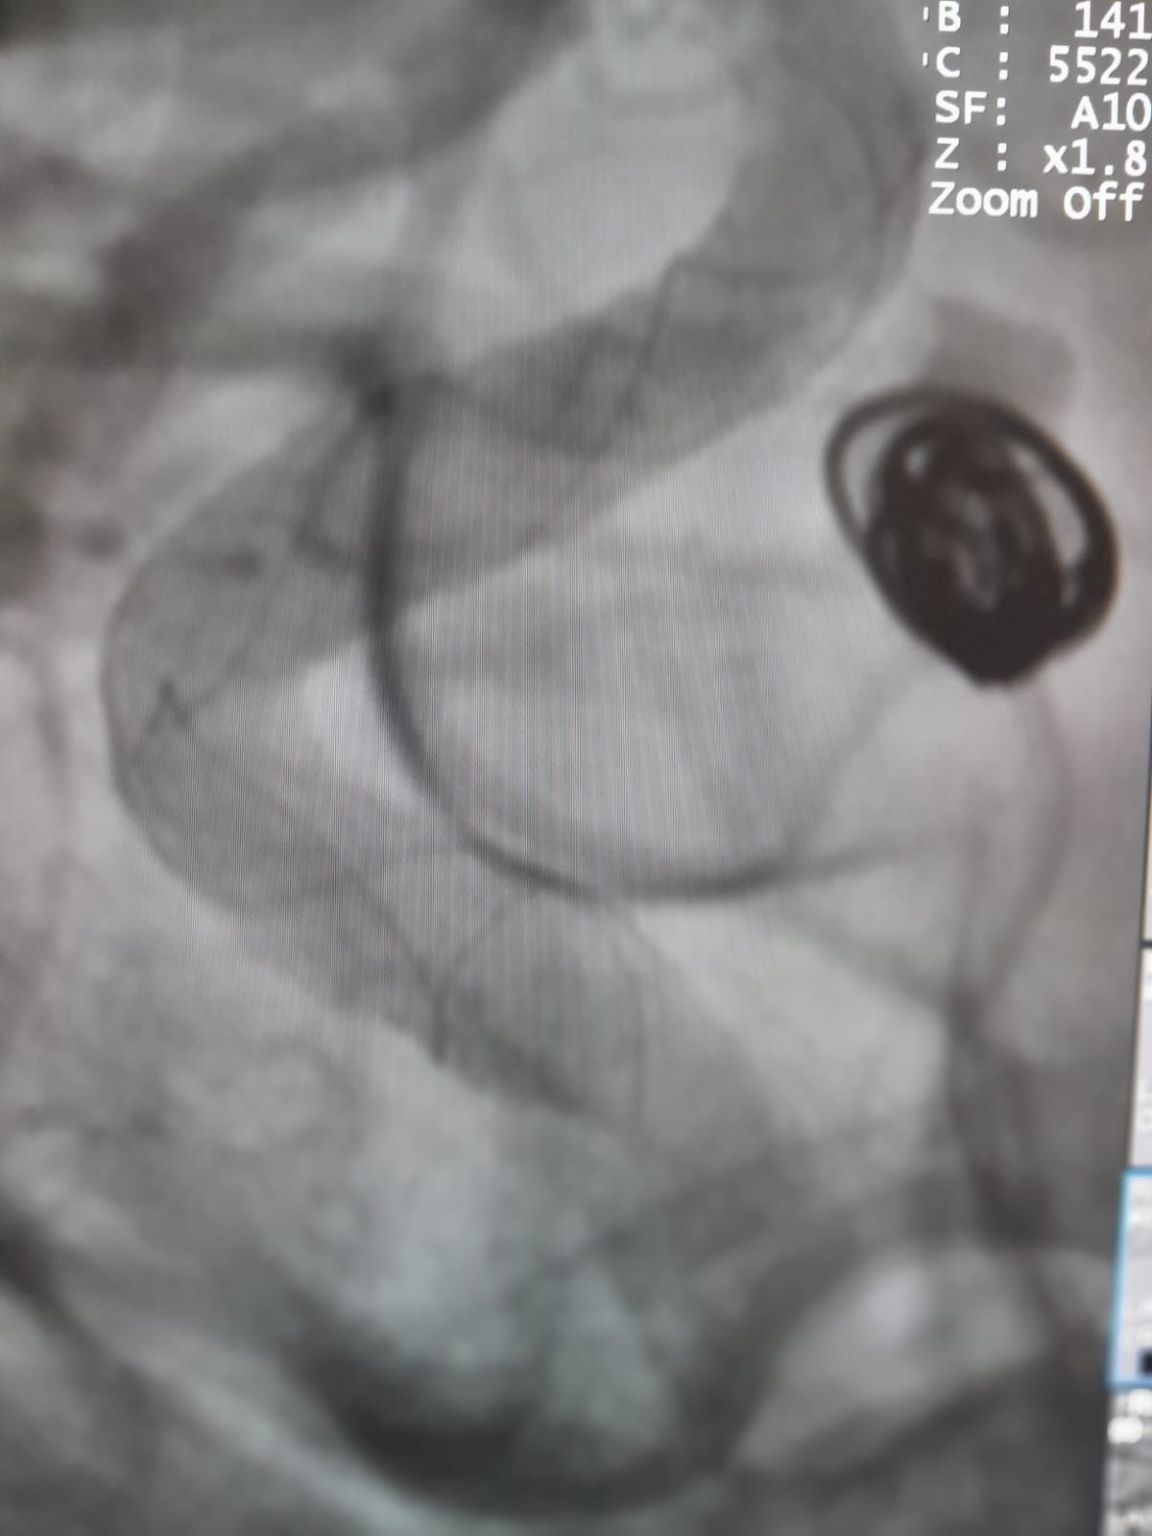

Anévrisme de l'artère communicante postérieure (retraitement)

Au cours du suivi, un remplissage résiduel a été noté dans l'anévrisme de l'artère communicante postérieure précédemment traité. L'équipe a réaccédé au site en utilisant Frepass®Microcathéter jetable (TJMC18 Plus) et a déployé avec succès un Nuva®Déviateur d'écoulement (TJED-D-4.5-16), qui a démontré l'apposition de la paroi idéale et une excellente dérivation de l'écoulement, conduisant à des résultats de traitement très satisfaisants.